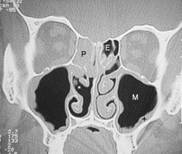

Abb. 1   Abb. 2

Abb. 2: Auf der rechten Seite des Bildes sehen sie verdickte untere Nasenmuschel und seitlich daneben die Kieferhöhle (M). Die Nasenatmung ist hier einseitig stark eingeschränkt. Die dünnen schwarzen Linien stellen die noch verfügbare Nasenatmung links dar!

Erklärung: Schwarz: Luft, Graustufen: Weichteile, Weiß: Knochen, IT: untere Nasenmuschel, M: Kieferhöhle, S: Nasenscheidewand